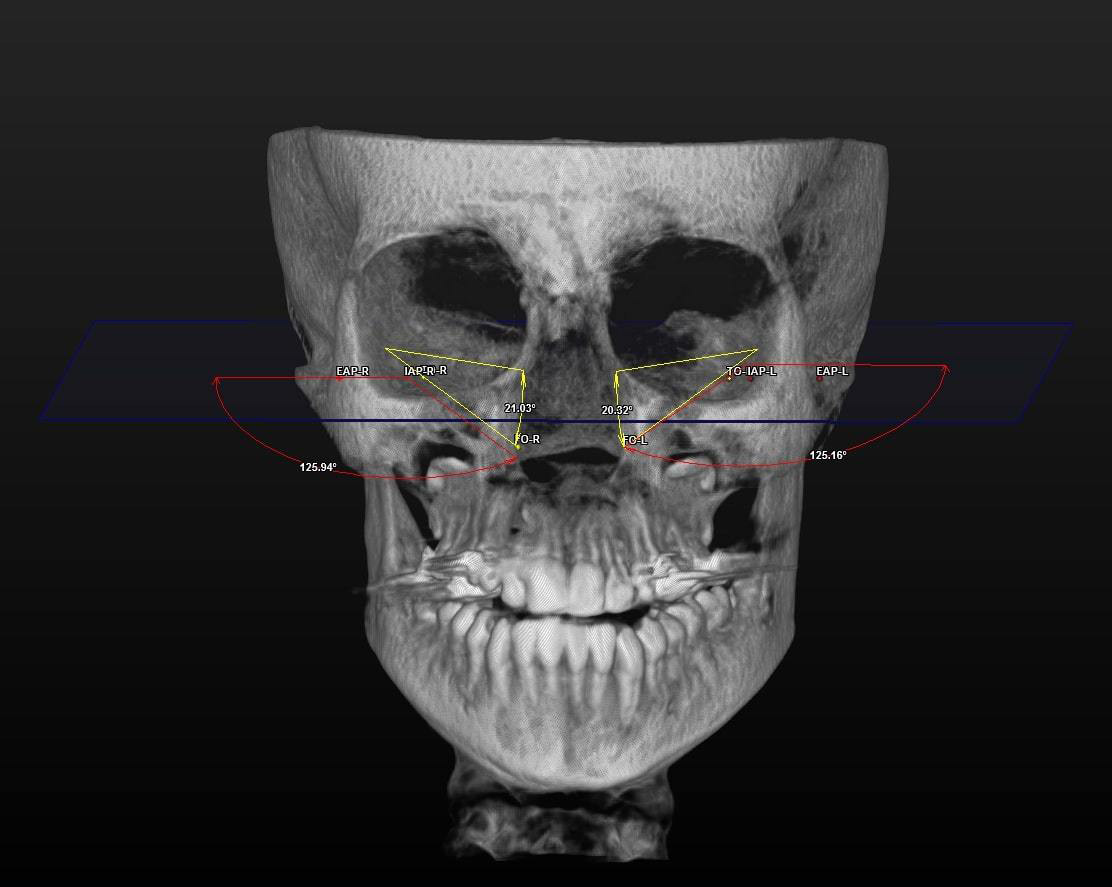

All 3D CBCT images were obtained with patients in a standing position using a CBCT device (ProMax® 3D Mid; Planmeca, Helsinki, Finland). The settings were as follows: 94 kVp; 14 mA; and 27 s. The images were consistent with the field of view (FOV) (20.0 cm × 20.0 cm × 10.2 cm) and voxel size (0.600 mm). The assessment of all CBCT images was conducted in 3D by a single clinician. The SimPlant® O&O image software (Materialise Dental N.V., Leuven, Belgium) was used for 3D image evaluation. The 3D morphological linear and angular parameters are listed in Table 1. The 3D morphological ET traces are displayed in Figure 1, Figure 2, Figure 3.

The comparison of the 3D linear and angular data is presented in Table 3. The mean right ET lengths were 36.26 ±3.10 mm at T0 and 36.13 ±3.08 mm at T1. Before and after RME, the mean left ET lengths were 36.82 ±2.98 mm and 36.82 ±3.12 mm, respectively. The right and left ET lengths did not differ significantly between T0 and T1 (p = 0.513 and p = 0.978, respectively). The mean right ET angle was 22.23 ±3.72° before RME and 22.82 ±4.06° after RME. At T0, the mean left ET angle was 22.33 ±4.22°. At T1, the mean left ET angle was 22.74 ±3.84°, indicating a non-significant difference (p = 0.077 and p = 0.184, respectively). The right auditory tube angle at T0 exhibited a significant increase compared to that at T1 (p = 0.000). The mean left auditory tube angles were 127.87 ±3.28° at T0 and 127.53 ±3.45° at T1 (p = 0.197).

Dinç et al. compared the ET angle and length in healthy subjects and those with otitis media. The ET angles in healthy individuals were 23.0° in females and 24.3° in males.25 The Frankfort horizontal plane was used when measuring ET angles. The angles in our study were slightly lower. In other studies, the mean ET angles with the horizontal palatal plane averaged 34–36° in adults.26, 27, 28 In adolescents, the ET angle with the Frankfort horizontal plane was approx. 22°. The difference may reflect age-related changes and the use of reference planes. The ET angle remained constant after RME on both sides. No prior study has measured the effect of RME on 3D ET angles. Therefore, there was no basis for comparison. We expected that any changes would be similar; symmetrical RME was applied to the mid-palatal suture. No differences in right and left ET length were observed between T0 and T1 (right: 36.26 ±3.10 mm at T0 and 36.13 ±3.08 mm at T1, left: 36.82 ±2.98 mm at T0 and 36.82 ±3.12 mm at T1; p = 0.513 and p = 0.978, respectively). Using two-dimensional images, Bluestone et al. found that the ET length increased as children grew, attaining a final size of 31–38 mm at approx. 7 years of age.12 Takasaki et al. used conventional CT to compare the ET length between children and adults; the ET length in children was 38 mm and 43 mm in adults.28 The CBCT data obtained in the current study was slightly different, presumably due to the imaging modalities. Ha et al. noted that the ET lengths revealed by conventional CT and CBCT differed due to subjects’ positioning, whether in a supine or seated posture.29 Ultra-low-dose CBCT has been demonstrated to optimally detect morphological structures and is associated with reduced radiation, sharper imaging and briefer viewing than CT. Many studies have shown that RME consistently reduces conductive hearing loss and improves ET function in adolescents with maxillary transversal constriction.30 However, the present study found no significant effect of maxillary expansion on the ET length. There are 2 possible explanations for this state of affairs. Other studies have collected audiometric or tympanometric data; however, these studies did not include 3D CBCT linear and angular measurements. Secondly, RME inhibits the infection of the nasal and pharyngeal airways, which may contribute to a reduction in the incidence of otitis. Maxillary expansion improves conductive hearing loss and reduces the incidence of otitis media.

Duman et al. used an identical CBCT protocol to determine the auditory angle, which was significantly larger in patients with cleft lip and palate than in normal individuals; such patients often exhibit a severe maxillary transversal deficiency.31 We also found that the right auditory tube angle was larger before RME in patients with maxillary constrictions. The effects of RME on Eustachian and auditory CBCT data require further research. Longitudinal studies would be instrumental in defining the effect of RME in patients without adenoidal or other nasopharyngeal disorders. The retrospective nature of the study constitutes a limitation, as it relied on a limited set of patient data. Additionally, the absence of auditory tests comparing measurements to patient data further restricts the study’s conclusions.